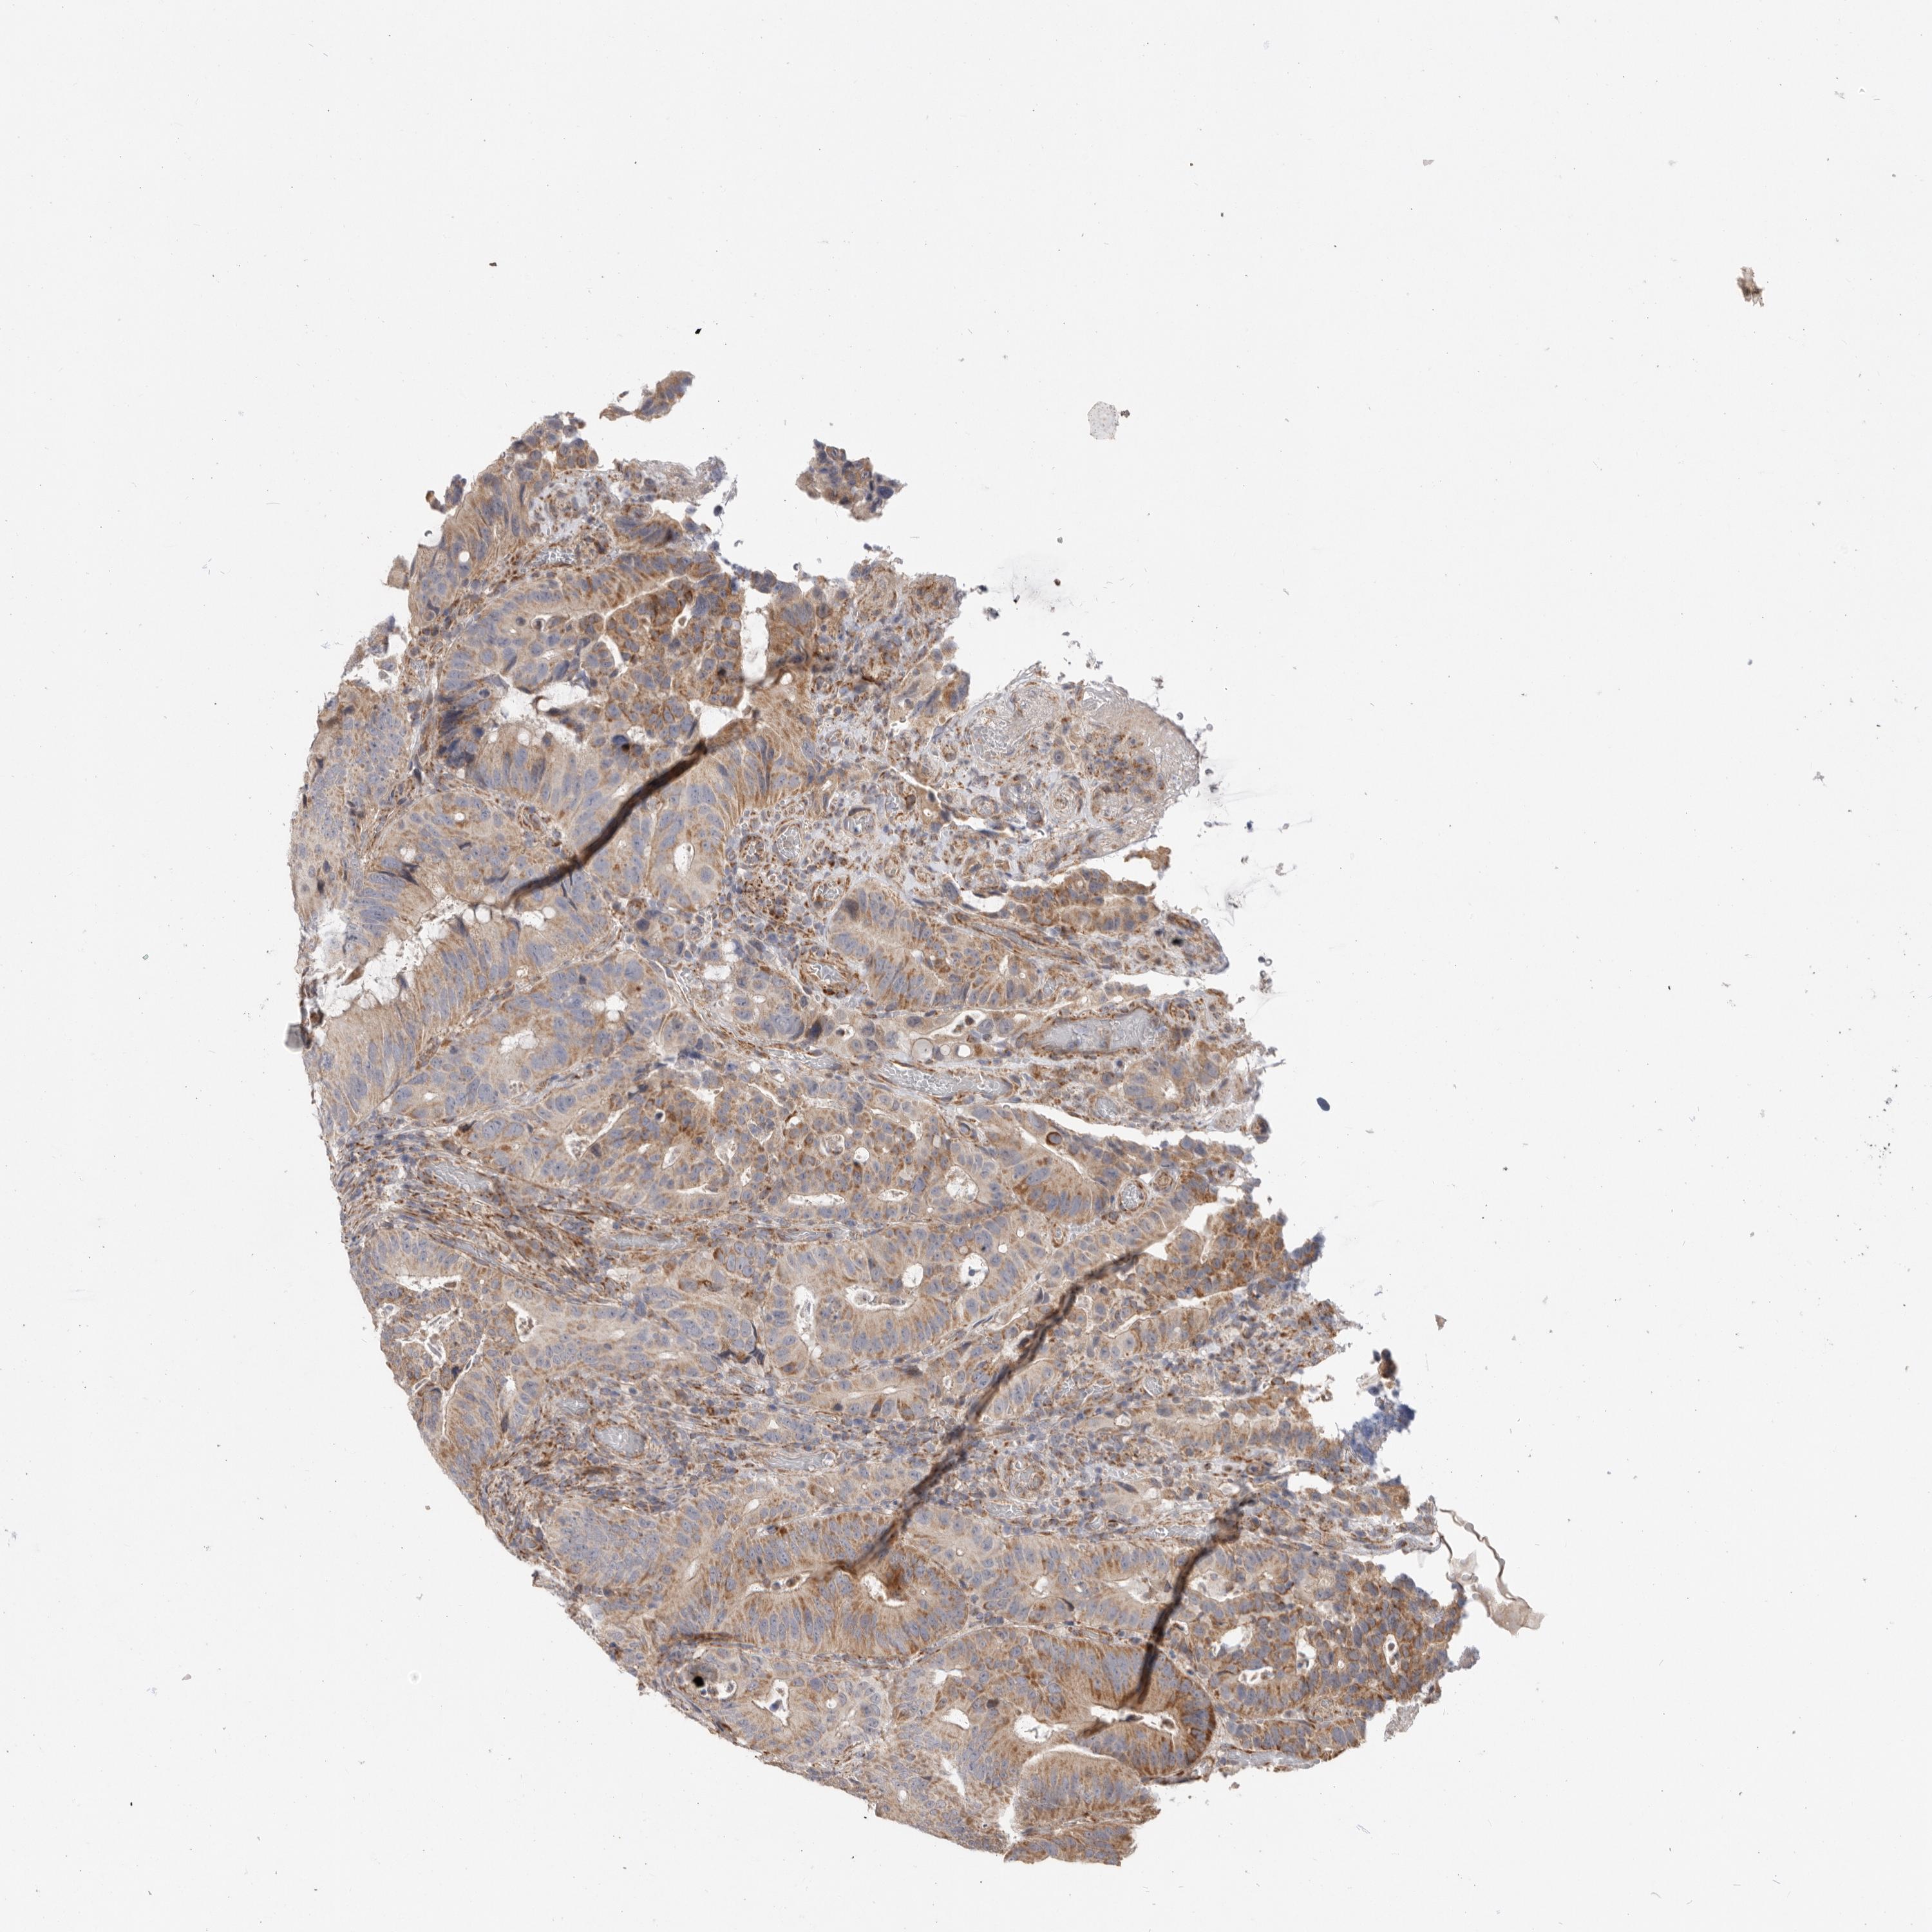

Colorectal cancer

Rectum adenocarcinoma